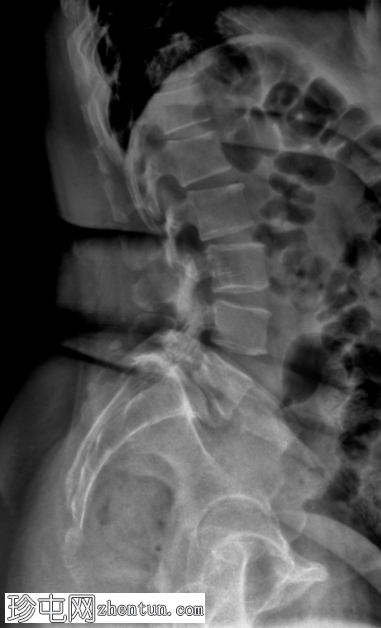

侧面

3.png

L5-S1 椎体II度滑脱。

双侧椎间盘缺损。

L5-S1椎间盘间隙缺失,伴有退行性病变。

脊柱动态成像(屈曲和伸展视图)有助于评估不稳定性,这种不稳定性在退行性脊柱疾病中最为常见。